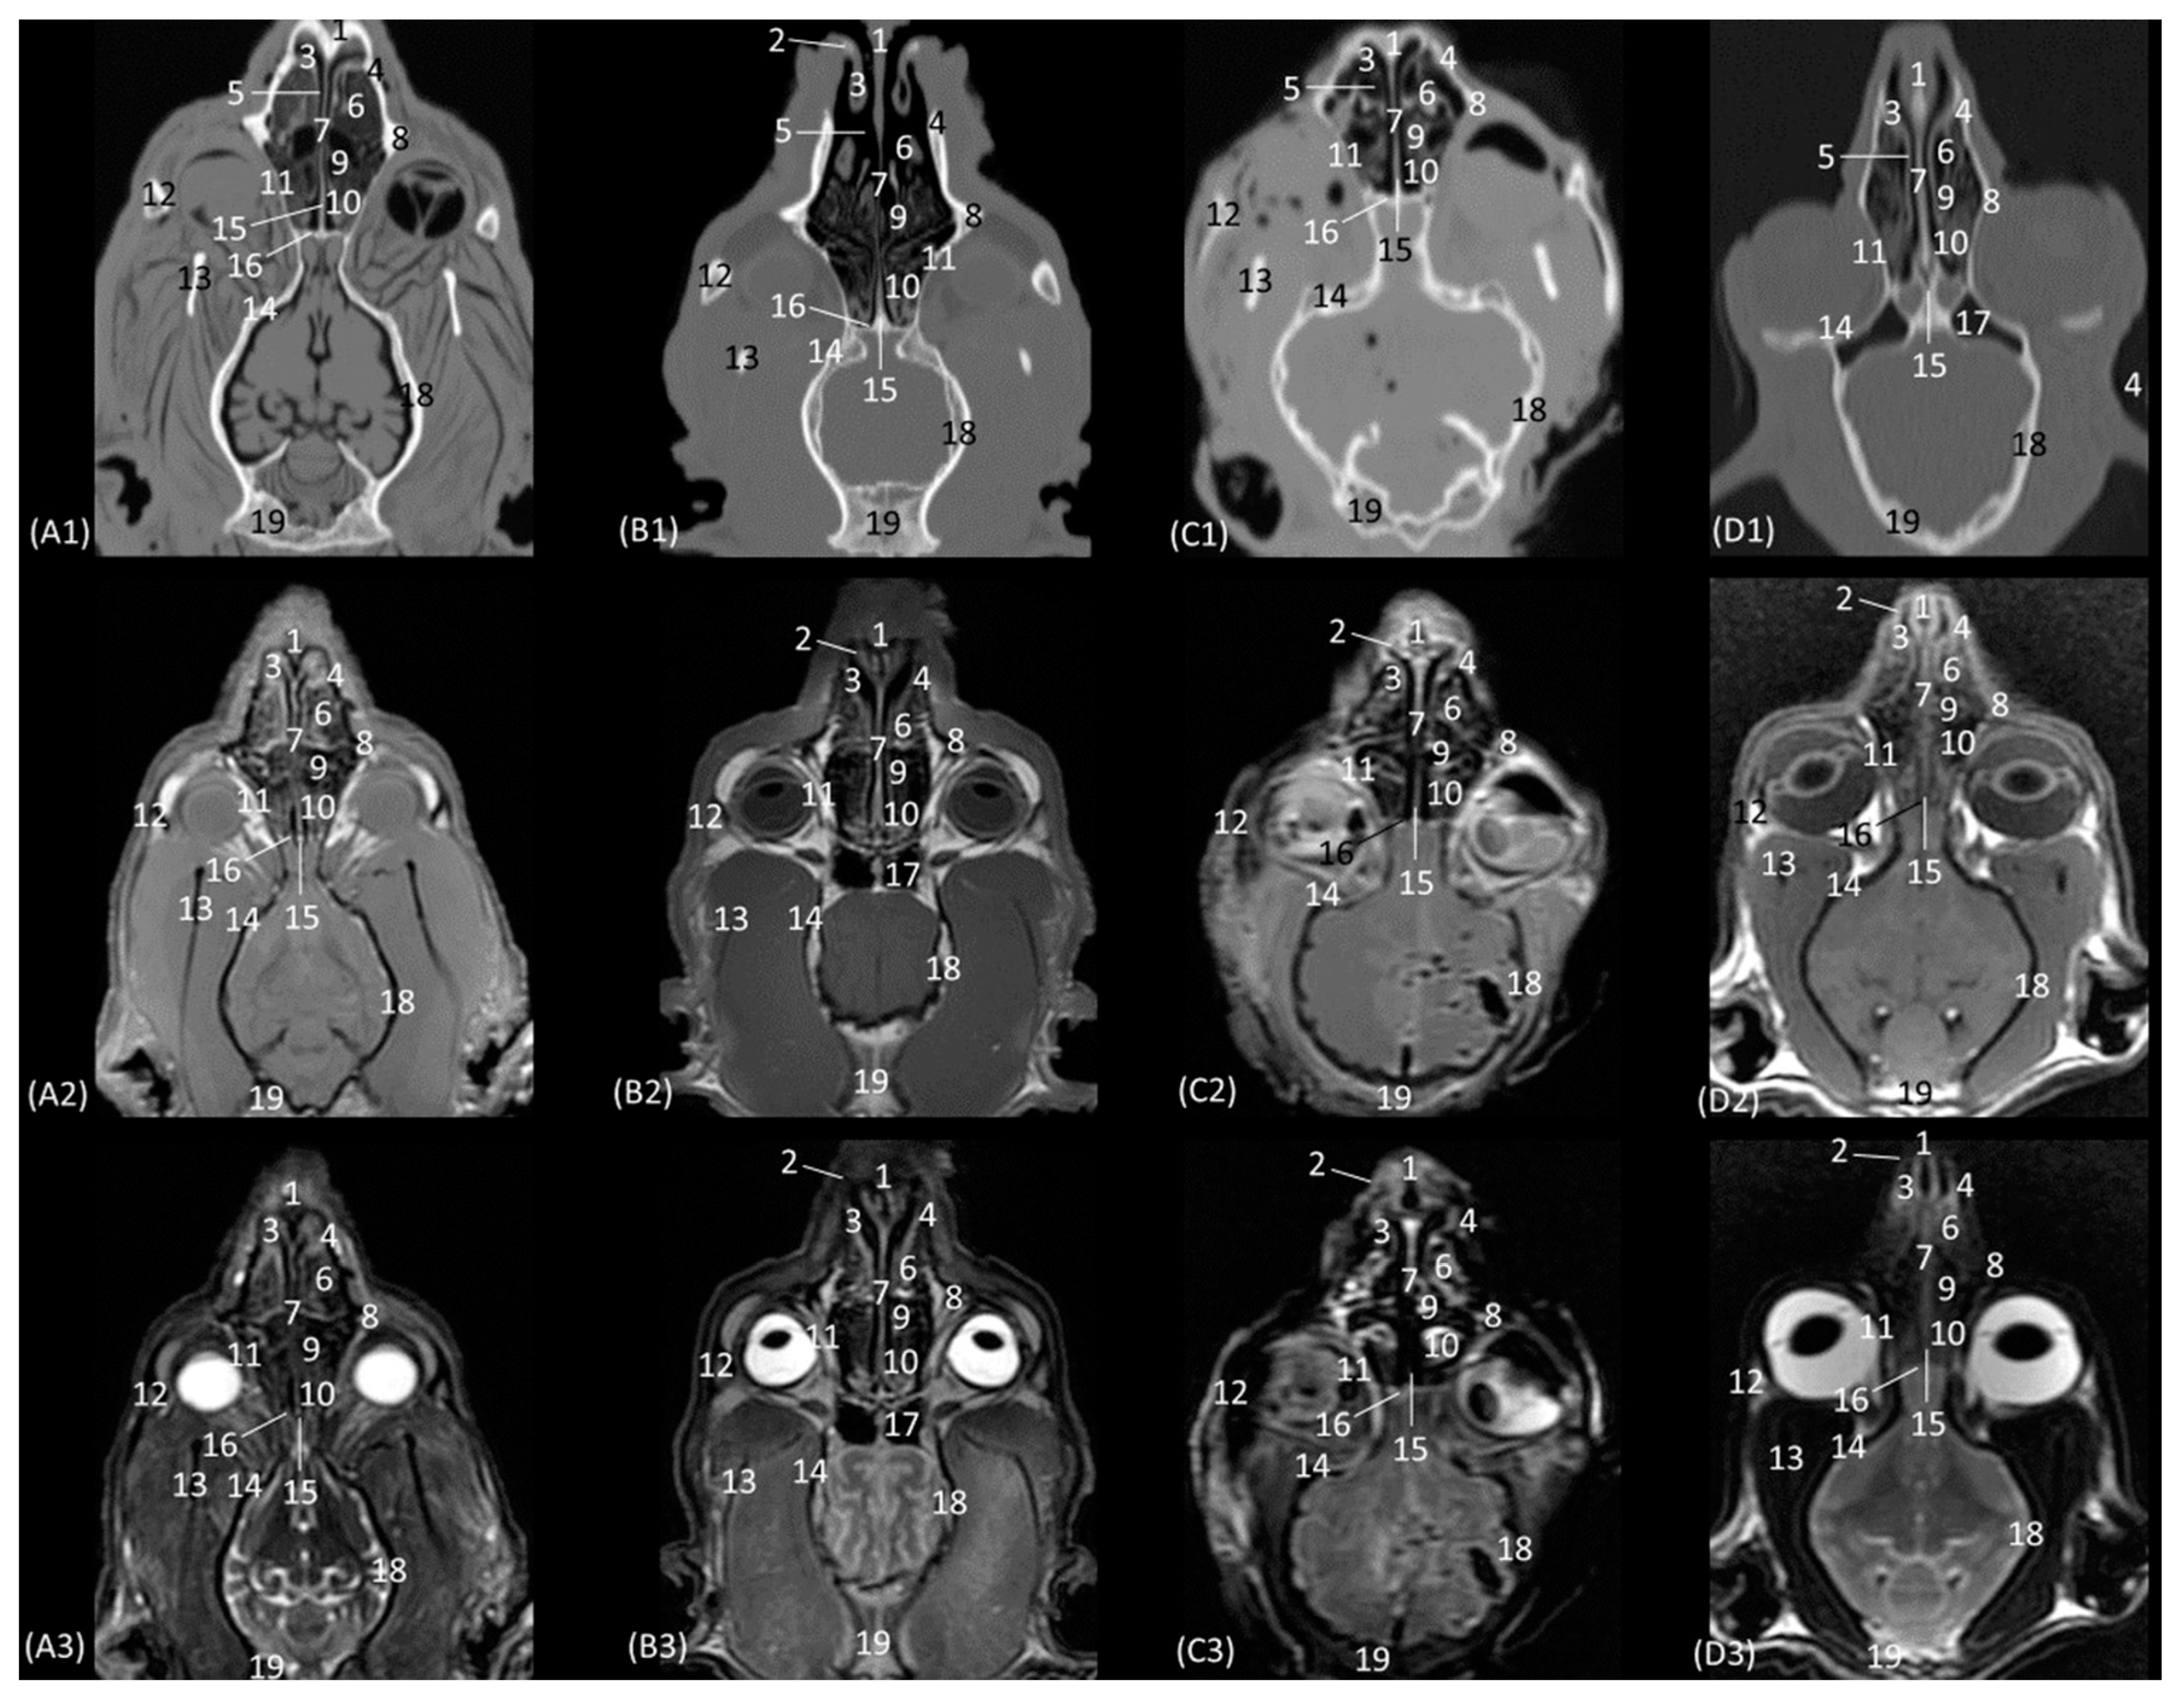

The anatomical level sections of the cat heads are shown in Figure 1. At the level of the nasal plane (Figure 2(A1–D3)), the development of the entire cartilaginous structure that forms the framework of the nose could be identified in the four studied feline species: dorsal and ventral lateral cartilage, lateral accessory cartilage, alar fold, and its corresponding alar groove, with an intermediate degree of attenuation and signal intensity in CT and MRI, respectively. In this context, it is worth highlighting the greater difficulty in identifying nasal cartilages on MRI compared to CT. On MRI, they are visualized as hyperintense lines with respect to the nasal wings that make up the opening of the nose. In contrast, it was observed that the conformation of the alar fold is more elongated and vertical in the lion and the cat, who have a much narrower space in the opening of the nose, than in the leopard and cheetah. Parallel folds were only identified in the leopard and the cheetah. The subnasal groove was visualized in the leopard by means of CT and MRI (Figure 2(A1–A3)) and less clearly in the cat by means of MRI (Figure 2(D3)).

The next plane shows the nasal vestibule (Figure 3(A1–D3)). The ventral limit of the beginning of the nasal cavity is established at the level of the incisive bone in the four species, with the cortical and medullary cavity being well differentiated on CT. The root of the upper canine tooth is also identified, as well as the maxillary bone. Unlike the CT study, MRI permitted the observation of the incisive bone with a hypointense cortical and a hyperintense trabeculated medullary cavity due to the fat content of the bone marrow. This view shows how, in contrast to the other three species, the maxillary bone of the cheetah already begins to project dorsally as the scan sequence progresses. The incisive bone forms the hard palate at the level of the nasal vestibule. At this section level, we can more easily observe the structures making up the nasal cartilages of the four species, observing hyperintense lines on MRI with respect to the surrounding tissue. The straight fold in the four species at this level is still poorly developed. However, the alar fold is very evident in this section, being much more curved in the cheetah than in the three other felids, in which it develops more vertically. The basal fold is much more developed in the domestic cat than in the other species. On the other hand, in the domestic cat, it can be observed that, proportionally, the nasal wing and the alar fold have a greater depth, since at the same level of the nasal vestibule, these two structures can be identified only in domestic cats (Figure 3(D2,D3)). The nasal cavernous plexuses already begin to become evident in the middle of the nasal septum, being less noticeable at this level in the lion than in the rest of the species studied.

The next section delves into the respiratory portion of the nasal cavity, since the nasal conchae are already beginning to be observed with intermediate attenuation and signal intensity in CT and MRI, respectively (Figure 4(A1–D3)). The bones that make up the floor, side walls, and roof of the nasal cavity are the incisive and vomer, maxillary, and nasal bones, respectively. At this section level, the maxillary bone can already be seen vertically, limiting the nasal cavity laterally and with the nasal bone marking its dorsal border. In the leopard and the lion, the most dorsal part is not visible, since the closure of the nasal bones extends more caudally in these two species. On MRI, both this dorsal limit and the junction between the maxillary bone and the nasal bone are difficult to differentiate, since both are hypointense. Within the nasal cavity, we can see the turbinates or conchae, the vomeronasal organ, and the nasal cavernous plexuses. The dorsal nasal concha of the big cats is identified as flat with only minimal extension into the nasal cavity. In the domestic cat, its development is proportionally much greater. The ventral nasal concha, with a dorsal and a ventral coil, is much more developed than the dorsal nasal concha, and it is slightly ossified at this level in all four species. This concha presents a similar morphology among the species of big cats, having a single start from the conchal crest of the maxillary bone while, at this level, a double start was identified in the domestic cat. These conchae create spaces in the nasal cavity: the dorsal, middle, ventral, and common meatuses, which are observed to be hypoattenuated in CT and hypointense in MRI. In the MRI study, they are not fully labelled to allow for better visualization of the rest of the structures. These spaces are described in all four species, but it is in the lion that they reach the greatest amplitude. At this level, the vomeronasal organ is very well identified; a hypoattenuated duct can be seen in the four species that we studied on CT, while on MRI, it appears slightly hypointense on T1-weighted and barely distinguishable on T2-weighted images. The vomer bone is located medially and has a groove for the support of the cartilage of the nasal septum. On CT, it is very well visualized in a hyperattenuated manner; however, on MRI, a small external hypointense cortical line is displayed, and internally, a hyperintense area, with much greater signal intensity, is seen in the T2-weighted images. It is attached to the maxillary bone and is clearly identified on CT, but on T1 and T2-weighted MRI, this bone is hypointense and is viewed with difficulty. The morphology of this bone is a “Y” shape in the leopard and the lion and more vertical in cats, with a double Y shape and being centrally fused with a stool shape in cheetah. The nasal cavernous plexuses at this section level are well distinguished dorsally and laterally to the vomer bone and are less developed on the lateral walls of the nasal cavity.

In the next section of the nasal cavity (Figure 5(A1–D3)), the conchae begin to appear slightly hyperattenuated on CT. The bones that make up the limits of the nasal cavity at this level are the palatine processes of the maxilla and the vomer bone at the base, the body of the maxillary bone laterally and dorsally, together with the nasal bone. It can be observed that the nasal bone is already closed dorsally in the leopard, while in the lion, it is not yet completely closed at this level. Within the nasal cavity, we can identify the dorsal nasal concha, the ventral nasal concha, and the third endoturbinate, as well as the nasal cavernous plexuses and the vomeronasal organ. At this level in CT, it is observed that the dorsal nasal concha is hyperattenuated in the leopard and the cheetah and slightly in the cat, but in the lion, the tissue continues to show an intermediate attenuation. With MRI, it is more difficult to identify this ossification, but a more hyperintense signal can be observed in the more cranial sections. This bony attachment of the dorsal nasal concha to the lateral wall of the nasal cavity is represented by the ethmoidal crest of the nasal bone. At this level, in addition, the maxillary recess begins to be observable in the four species. The nasal cavernous plexuses continue to be identified in all four species, which is also evident in the ventrolateral wall, with less development in the lion and the cheetah. The third endoturbinate also begins to appear at this section level between the dorsal and the ventral nasal concha in the leopard, the cheetah, and the cat, but not yet in the lion. The vomeronasal organ in the leopard is a large-caliber duct, unlike in the cheetah and the domestic cat. It is topographically next to the long central stem of the vomer bone, which is concave and supports the base of the cartilage of the nasal septum, while in the lion, the concavity of the groove is formed without a bone stem from the maxillary bone.